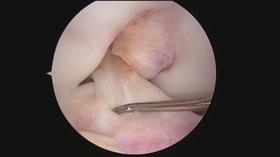

Our scopes are designed for use with either the LENS HD or LENS 4K Surgical Imaging System to increase brightness,*1,2 optimise colour transmission**1-3 and improve overall image quality.***1-5